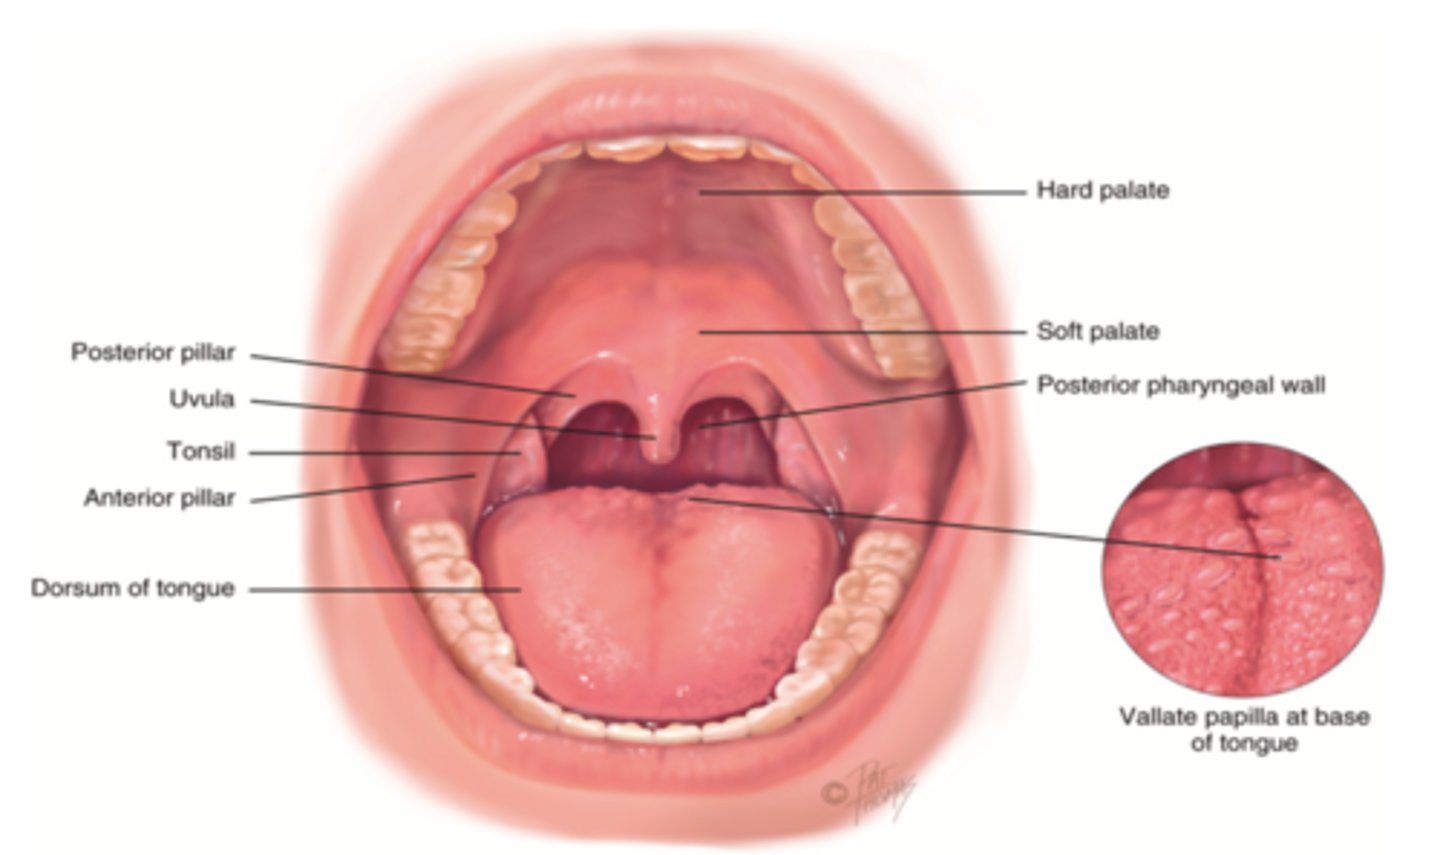

Oral Cavity

Mouth

Uvula

Soft tissue hanging from the middle of the soft palate

Amount of Teeth in Adults

32

Amount of Teeth in Babies

Pharynx (Throat)

Passageway for air, leads to trachea

Function of Throat

- Passageway for food

- Passageway for air

- Tonsils are part of the immune system

Nasopharyx

The portion of the pharynx that extends from the nostrils to the soft palate

Oropharynx

Central portion of the pharynx between the roof of the mouth and the upper edge of the epiglottis

Tonsils

Masses of lymphatic tissue in the back of the oropharynx

3 Tonsils in the Mouth

- Palatine

- Adenoid

- Lingual

Palatine Tonsil

One of a pair of almond-shaped masses of lymphatic tissue in the oropharynx

Adenoid Tonsil

Pharyngeal tonsil

Lingual Tonsil

Tonsil located at the base of tongue